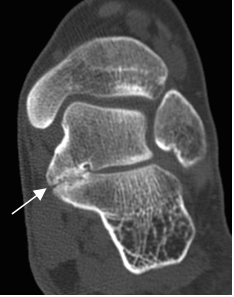

Fig 136 A. Coalición fibrosa del tarso.

A: TAC reconstrucción coronal. Disminución del espacio talocalcáneo medial, con esclerosis e irregularidad de los bordes, por coalición fibrosa.